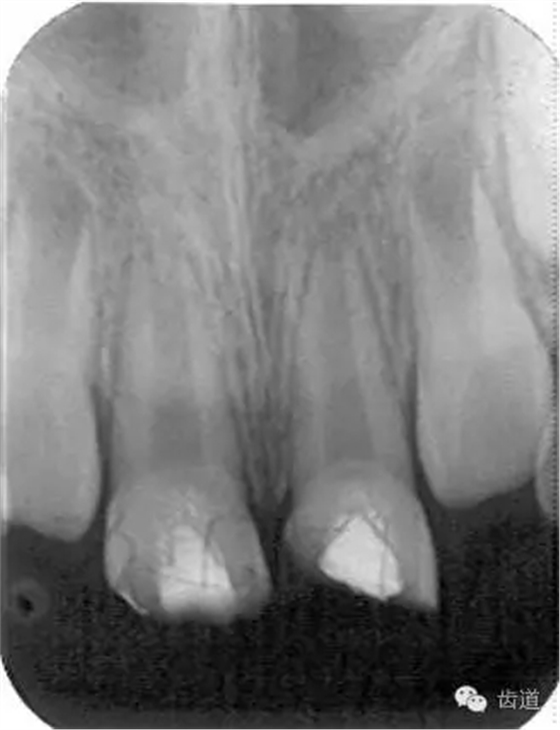

術(shù)后三個(gè)月

術(shù)后六個(gè)月

術(shù)后兩年